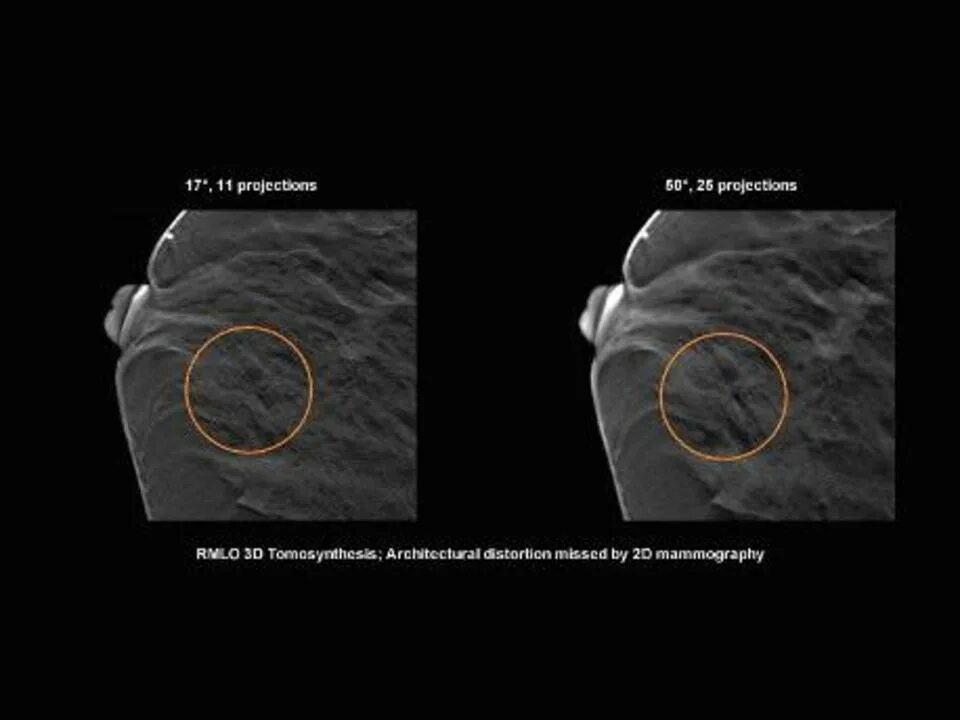

Делают ли мрт молочных желез